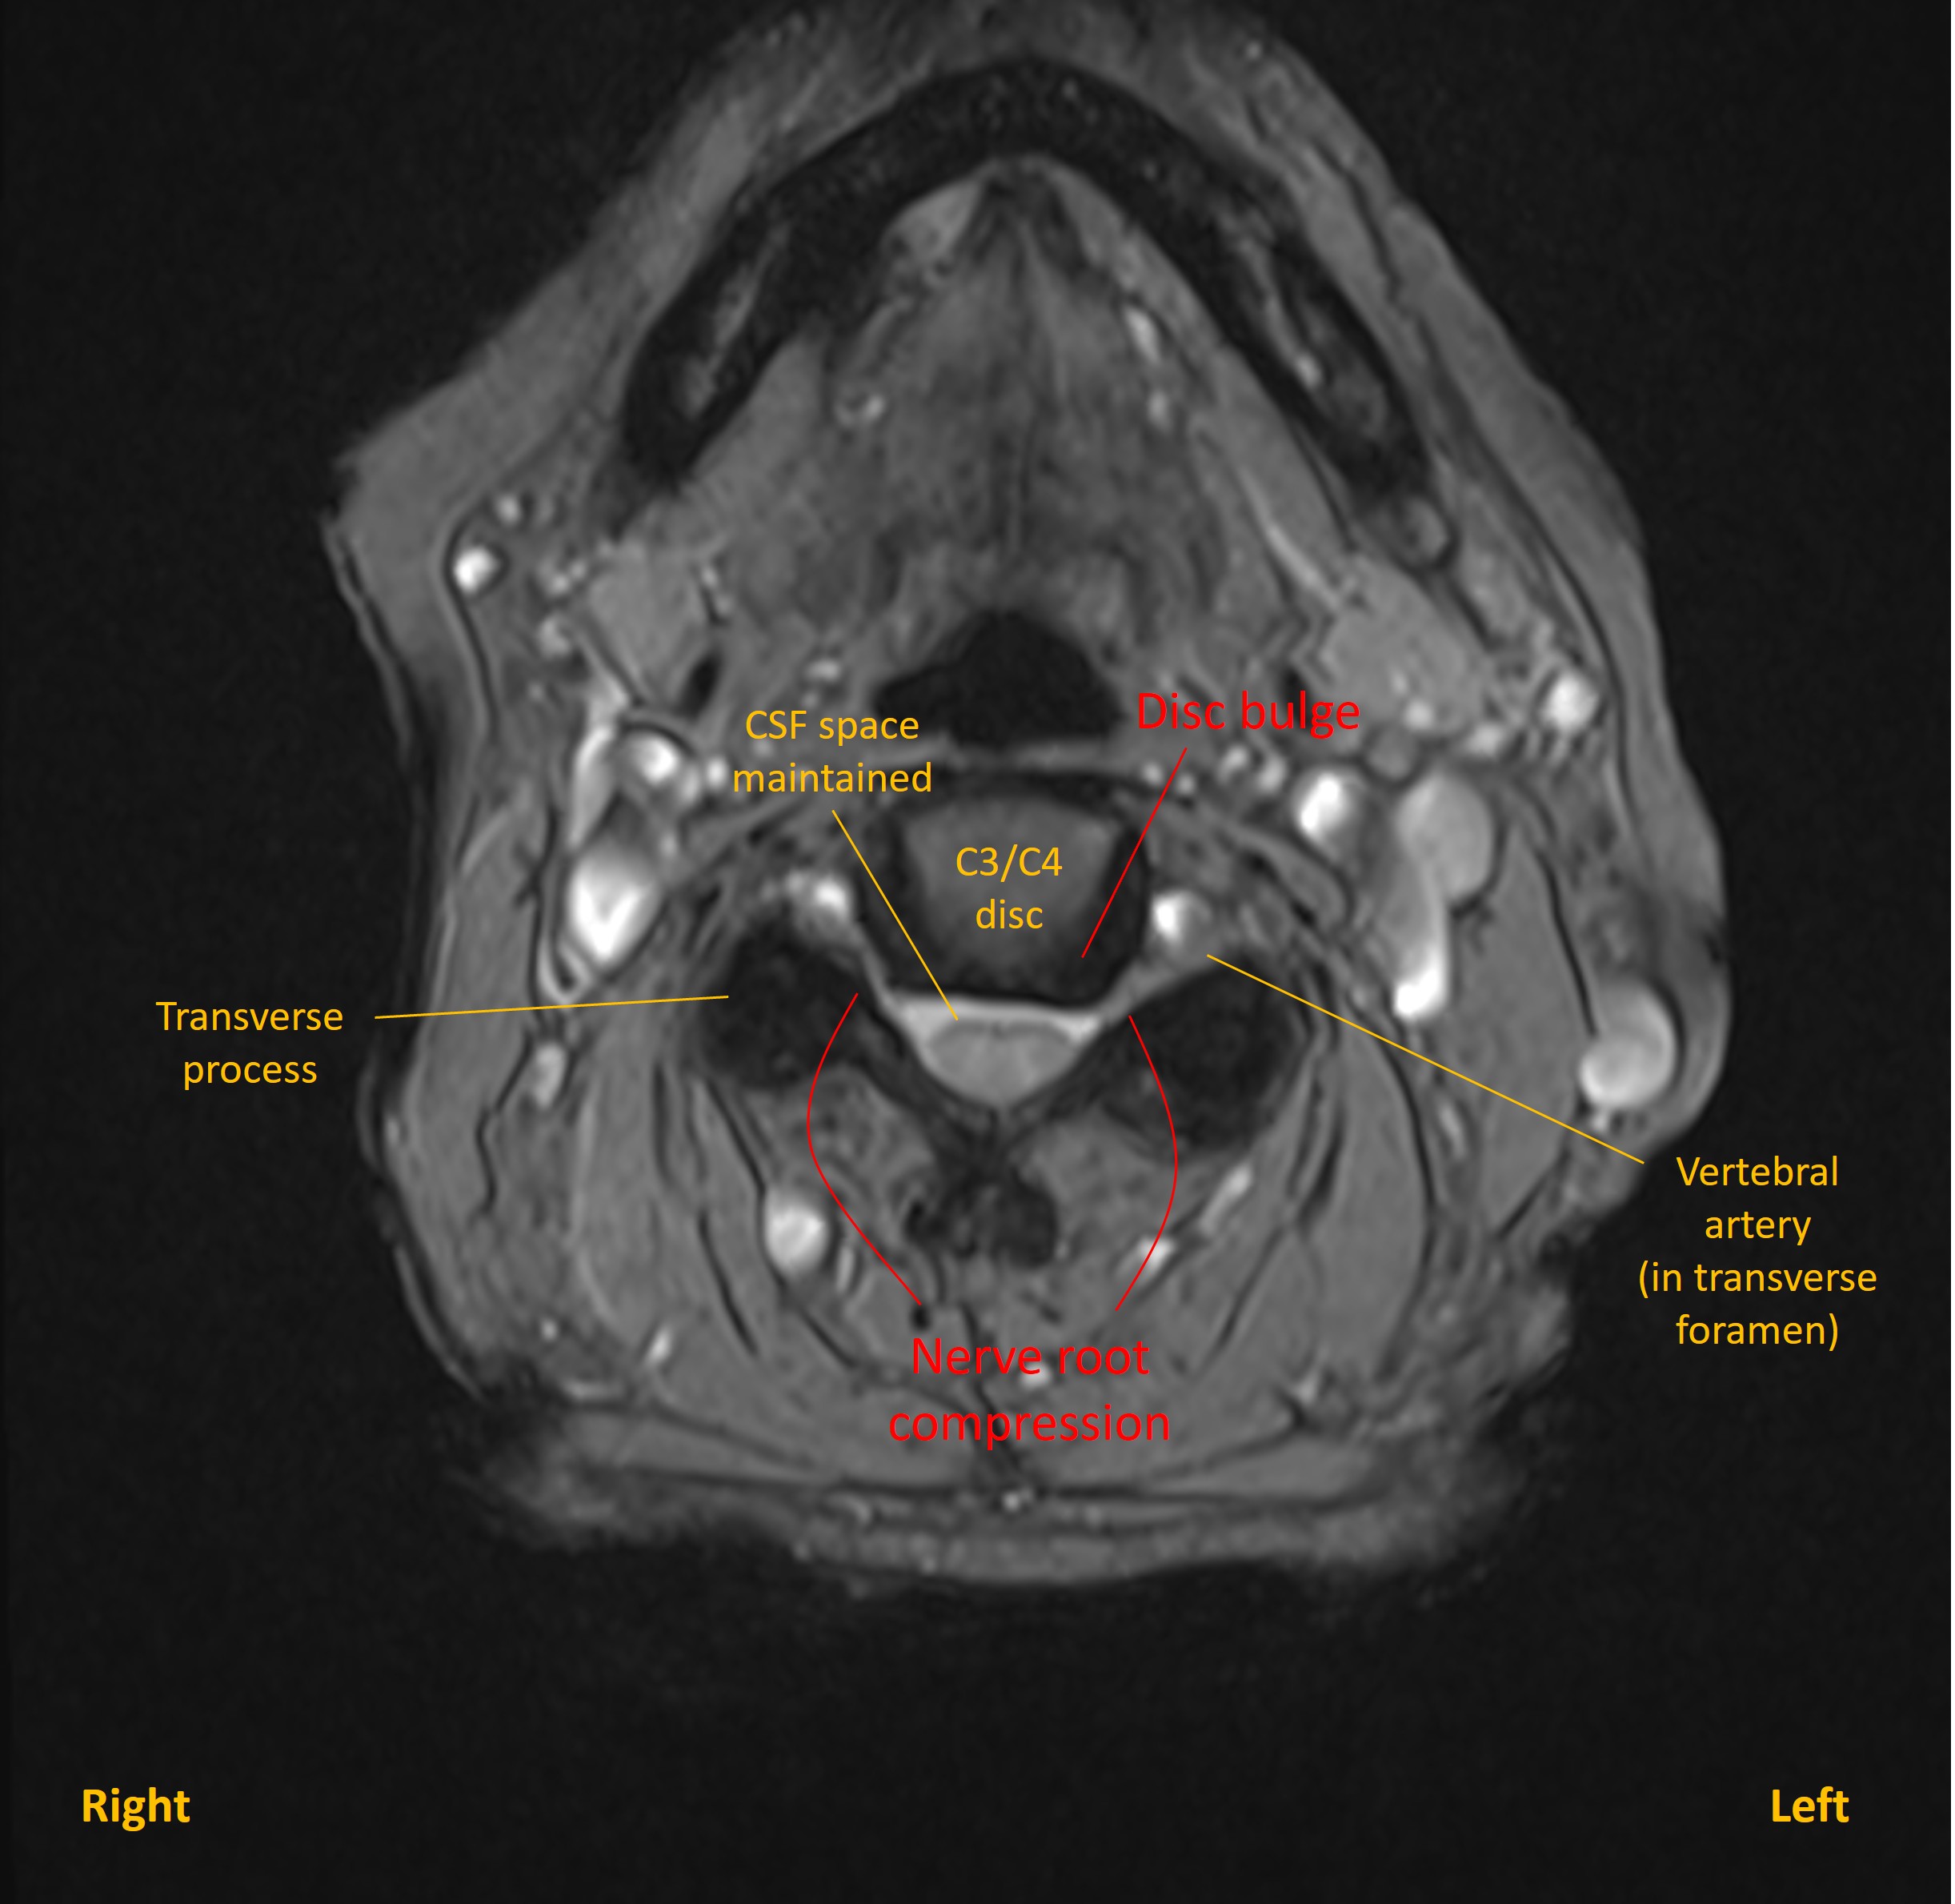

Degenerative changes were seen at multiple levels in the cervical spine, as is frequent at this age, and with some levels featuring mild narrowing of exit foramina and contact with nerve roots. These were evident at levels C3/C4 (B), C4/C5 (C) and C5/C6(D) - although none of these were clinically evident. Disc bulges at other levels did not compress the cord.

Axial MRI